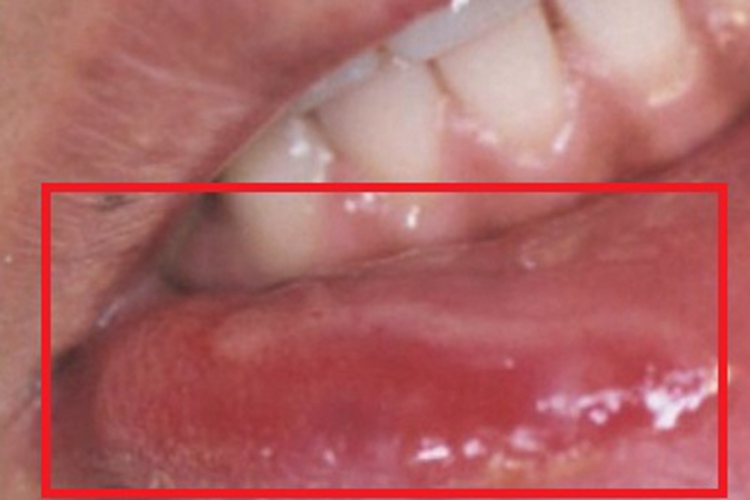

梅毒性唇下疳可引起患处出现不同程度的肿胀,表面发红并稍隆起,范围、大小不定,形状不规则,表面可有灰白色、光亮而微隆的斑块形成,表面覆盖灰白色假膜,边界清楚,质地较硬。